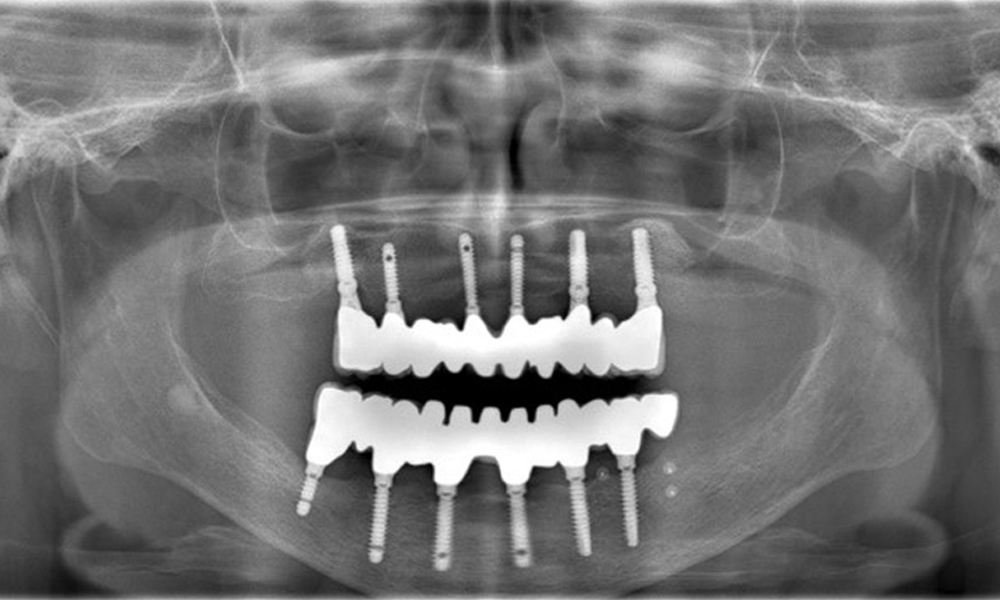

Figure 1: Periodontal Status (ParoStatus®.de)

The radiographic images reveal bone resorption.

Figure 2: The radiographic images reveal bone resorption.